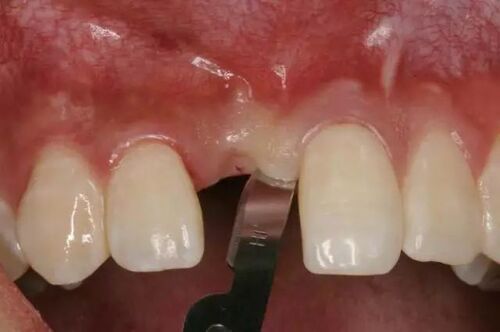

图4 分离后且非常清晰的下牙槽神经

下牙槽神经被提起后,骨板上的凹槽显露出来。进一步对CT图像进行检查,确认下颌神经从颊侧骨板穿出,并且在神经与囊肿之间存在正常骨质,下颌神经在一个开放的通道内自由移动。

这个放射学发现得到了临床验证:在摘除囊肿后,仍然存在坚实的骨质,左侧下颌神经的放射学检查显示其解剖结构正常。为了保护下颌神经,实施了牙冠切除术,并缝合了术区。术后3个月复查未发现下牙槽神经分布区域有感觉异常,复查的全景片显示骨愈合良好,剩余牙根位置稳定。组织病理学特征与牙源性囊肿一致,囊壁存在慢性炎症浸润,并被炎性鳞状上皮覆盖。